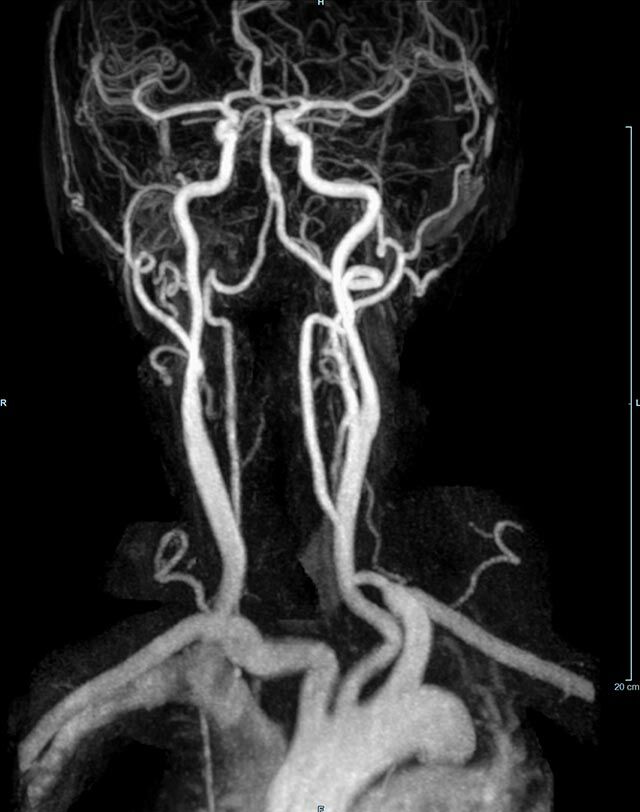

Halsgefäße

• intrakranielle Gefäße (Abklärung Verschluss, Stenose, Aneurysma)

• Halsgefäße zur Therapieplanung (z.B. Stent, Operation)

MR-Angiografie (MRA)

Angiographie ohne Kontrastmittel

• MR-Angiografie ohne Kontrastmittel

• Time of Flight (TOF)-Angiographie

• Phasenkontrastangiographie (PCA). Geeignet zur Quantifizierung Stenose-/Insuffizienzgrad z.B. bei Herzklappen, falls echokardiographisch die Untersuchungsbedingungen eingeschränkt sind.

Je nach Fragestellung und Körperregion Gefäßdarstellung ohne Kontrastmittel bei Kontrastmittelunverträglichkeit oder terminaler Niereninsuffizienz möglich.